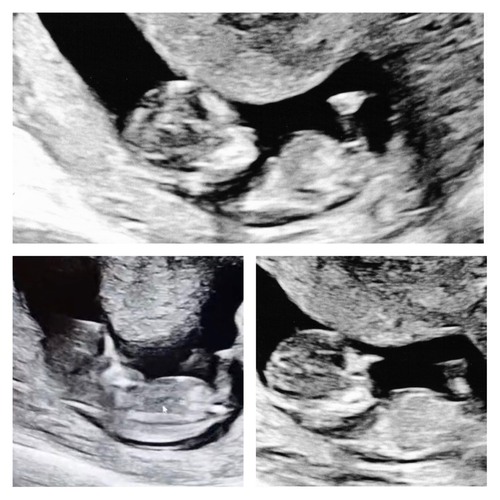

Hier heb ik nog een paar foto’s erbij maar denk dat die ene die ik eerder al stuurde het meest duidelijk is. Ik ben benieuwd wat jullie denken!

Hier heb ik nog een paar foto’s erbij maar denk dat die ene die ik eerder a ...